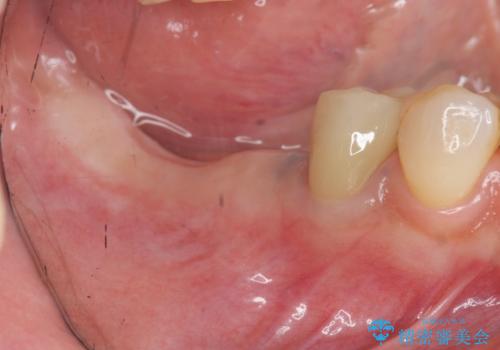

- 「数年前に入れたブリッジがぐらぐらする、診て欲しい。」と来院されました。

ブリッジを支える歯が割れてしまい、抜歯が必要であることと、骨の大きな吸収が見られました。